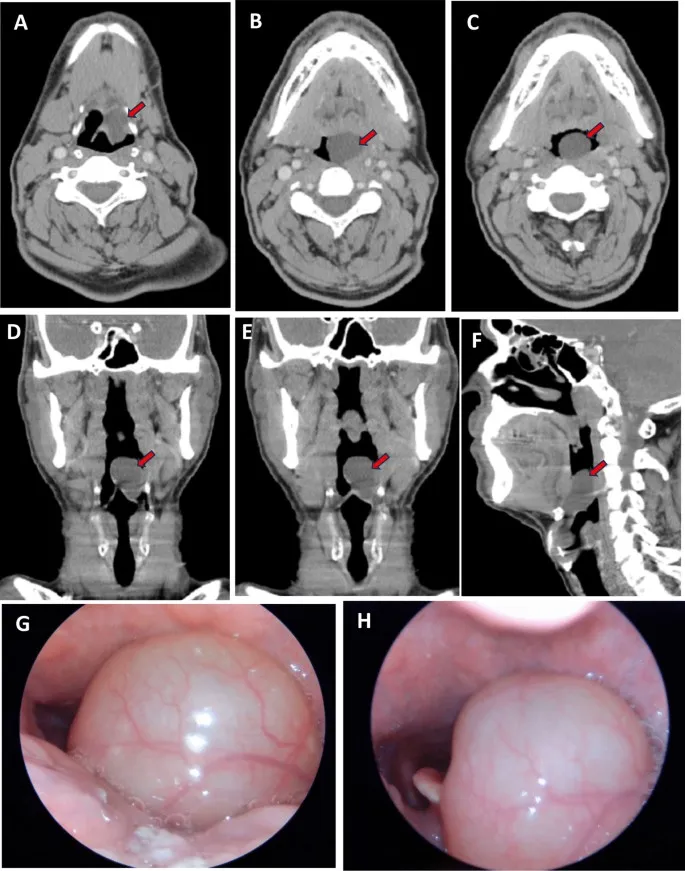

- CECT Neck & Chest: Assesses primary tumor (T), nodal status (N), distant metastases (M).

- MRI: Superior for soft tissue extension, perineural invasion, cartilage involvement.